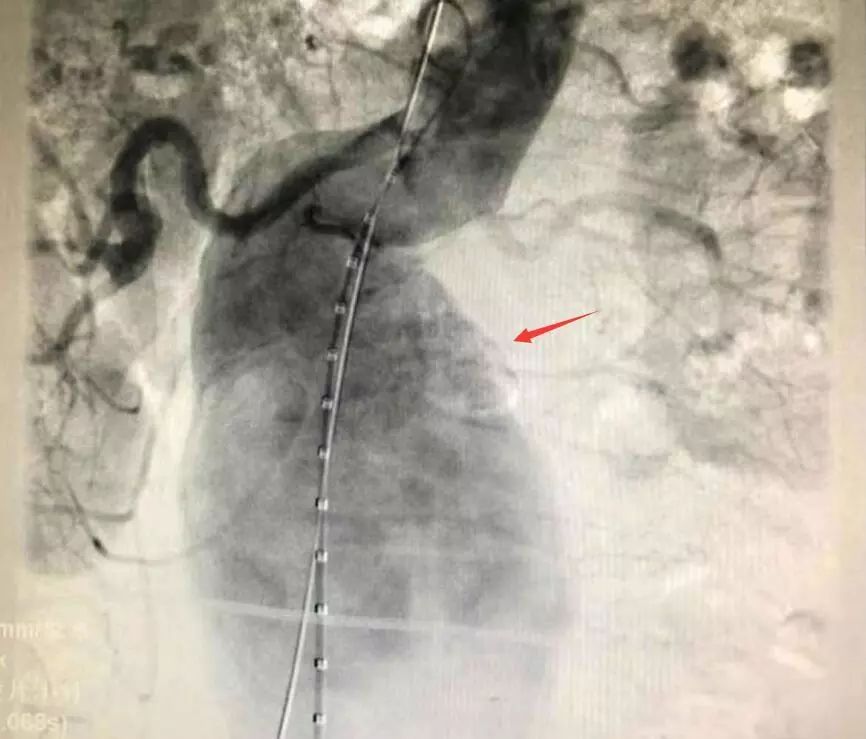

腹主動(dòng)脈CTA圖像

患者動(dòng)脈瘤呈梭形

動(dòng)脈瘤術(shù)中顯影